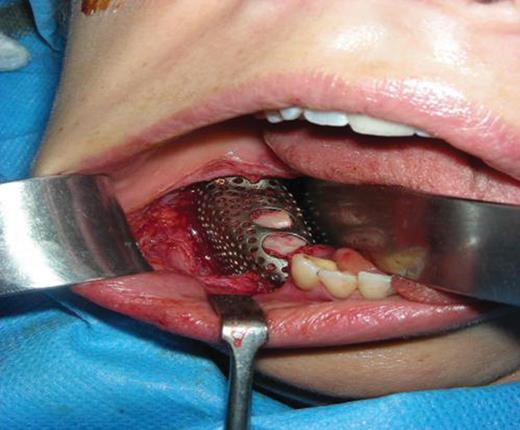

Previously, using CT scans, a titanium construct was made to guide the outline of the bone graft and complete the missing height and width of the mandible [3]. Once fitted to the patients jaw, it was packed with the bone graft and screwed down into position (Fig. 5). A slight groove was made on the mandible to allow space for the inferior dental nerve to lay, so that the construct did not compact the nerve and cause functional problems.

Titanium construct packed with iliac bone graft and screwed into position on the lower mandible

To complete the surgery, the periosteum was sutured over the construct and then the buccal muscosa was sutured over again to form a double-layered closure (Fig. 6a–c).The purpose of this was to prevent infection and rejection, by ensuring that there was an increased distance between the foreign object (titanium construct) and the outside environment. The dental implants are scheduled to be inserted several months after this operation.